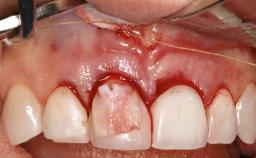

Treatment of Peri-Implant Mucositis at a Zirconia Implant

Recent clinical studies, most with short-to-medium term observation periods, have reported on the favorable clinical performance of zirconia implants in terms of survival rates, clinical, and radiographic outcomes (Roehling and coworkers 2016; Roehling and coworkers 2017; Rodriguez and coworkers 2018; Lorenz and coworkers 2019). Nonetheless, a rather high incidence of peri-implant disease at zirconia implants (39% of implants) was noted throughout a two-year period, highlighting the need for treatment protocols of peri-implant diseases at zirconia implants (Becker and coworkers 2017).